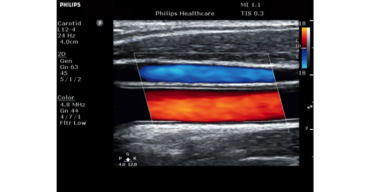

ecografo PHILIPS Clearvue 550

Progettato pensando alle esigenze di chi lo utilizza. Il sistema ecografico ClearVue 350 con tecnologia Active Array, che integra nel trasduttore le tecnologie fondamentali, garantisce una qualità eccellente delle immagini in uno strumento efficiente , affidabile ed estremamente compatto.

Tutti i prodotti Clearvue sono pensati per estendere le possibilità ecografiche a un’ampia gamma di applicazioni e di poter crescere in base alle tue esigenze.